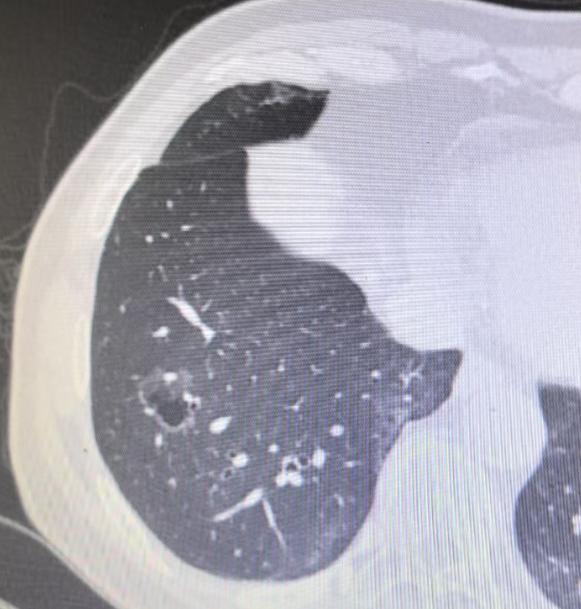

3个月前门诊遇到一位30岁的女士,由她先生陪着来的。她手里拿着外院的CT报告,声音都有点发颤:“医生,他们说我这右下肺的混合磨玻璃结节,可能是肺癌……” 看得出她已经焦虑了好几天,整个人显得很疲惫,她的先生坐在旁边,神情也非常凝重,手不自觉地攥着。 我仔细看了她的影像,结节的尺寸不算大,形态也有一定的特征。很多人都知道“混合磨玻璃结节”这个词很敏感,网上信息也复杂,容易自己吓自己。 但根据我的经验,首次发现的、小于1厘米的磨玻璃结节,真的不必第一时间就往最坏的方向想。 我告诉她:“先别急,不管是良性还是恶性,只要结节还小,我们完全有观察的时间。 我建议你给自己一次机会,也别急着手术,咱们3个月后来复查一次CT,看看它的变化,再定下一步计划。” 当时我还补充了一句,“以我的经验看,这个结节很有可能会自己消失。” 她听了这话,眼神一下子亮了,反复问我:“真的有可能吗?不需要现在就处理吗?”我给了她非常肯定的答复:“放心,我会对你负责,如果真有风险,我绝不会让你等。” 最近她如约来复查,结果特别让人欣慰——肺结节真的完全消失了,影像上看不到任何痕迹。她特别高兴,激动地向我道谢,整个人的状态和第一次来时完全不一样。 通过这个真实的案例,我想对大家说:查出肺结节先别慌,它远没有想象中那么可怕。很多结节其实是良性的,甚至可能自行吸收。即便是需要处理的磨玻璃结节,生长也非常缓慢,有充足的观察时间。即使最后需要手术,这类结节的治愈率也极高。 放平心态,给自己和医生一点观察的时间,很多时候,情况并没有我们一开始想的那么严重。[作揖][玫瑰]肺结节[超话]胸外科乔贵宾医生